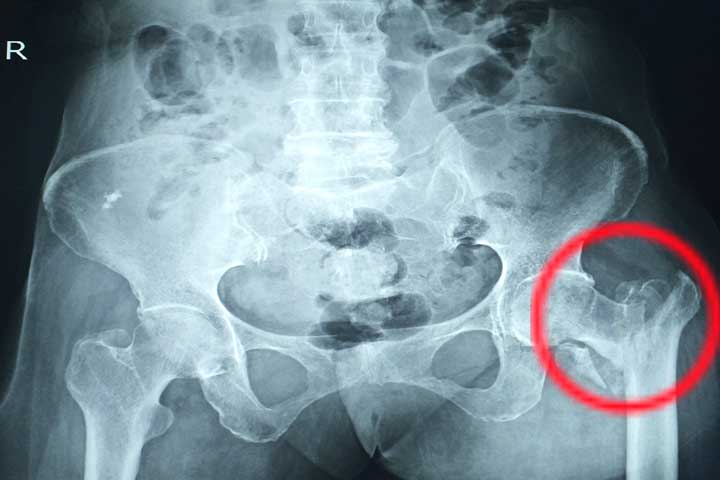

تعتبر جراحة العظام من أهم الاختصاصات في ألمانيا وأكثرها انتشاراً. الغالبية العظمى من المستشفيات تستقبل في قسم الإسعاف مرضى الحوادث والكسور والإصابات، ولذلك فإن هذا التخصص مطلوب جداً في ألمانيا.

تشمل جراحة العظام في ألمانياً مجالين: المجال الأول هو جراحة الحوادث أو الكسور (Unfallchirurgie)،أما المجال الثاني فهو عمليات العظام أو المفاصل الباردة (Orthopädie).

تشكل زيادة أعمار السكان وبالتالي تعرضهم للسقوط والكسور وكذلك التنكس المفصلي أحد الأسباب المهمة لشيوع عمليات الجراحة العظمية في ألمانيا

تبلغ مدة تخصص جراحة العظام ست سنوات، يحصل بعدها الطبيب على شهادة طبيب اختصاصي بجراحة الحوادث والعظام (Facharzt für Unfallchirurgie und Orthopädie)يمكنه بعدها إن أراد تعميق التخصص في عدة مجالات فرعية ذكرنا بعضها في صندوق المعلومات أدناه.

من الفروق المهمة بين جراحة العظام في ألمانيا والدول الأخرى هي أن طبيب جراحة العظام أو الحوادث يقوم أيضاً بمعالجة أمراض وكسور العمود الفقري. وهناك في بعض المستشفيات أقسام متخصصة بجراحة العمود الفقري تحت إشراف قسم جراحة العظام.